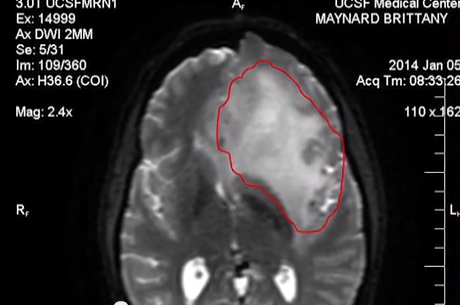

One of the most incurable forms of cancer remains brain cancer and the average brain cancer survival rate period is 1-2 years. Still today, there is no recognized cure for this disease. Although treatment helps to improve the condition of the patient a little, there is no guarantee that it will be cured. Eleanor Mondale,  […]